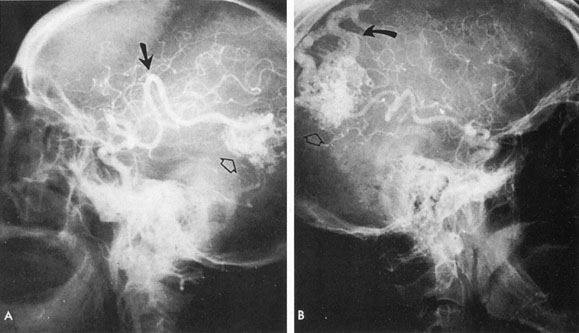

Of particular interest are those AVMs that involve the occipital lobe (Fig. 9). The clinical differentiation of migraine from a cerebral AVM was previously regarded as difficult because the clinical features of occipital lobe AVMs include visual phenomena or headaches. However, in most cases the clinical distinction is possible. In 26 cases with occipital AVM, two distinct syndromes were defined in 18 patients: occipital epilepsy and occipital apoplexy.73 Focal seizures with occipital malformations consist of elementary visual sensations similar to the phenomena evoked by direct cortical stimulations. When seizure activity occurs in the striate cortex (area 17), the patient usually reports sensations of moving lights in the right or left homonymous fields. The sensations are poorly formed, episodic, usually brief, sometimes colored, and unassociated with the angular, scintillating figures so characteristic of migrainous cortical phenomena. Epileptic discharges from areas 18 and 19 cause photopsias that are unlikely to remain stationary and to flicker rapidly. The epileptic photopsias usually last only seconds; occasionally they last for a few minutes before the onset of a generalized seizure. In other instances only the brief visual episodes occur without spreading to produce a generalized seizure. Momentary dimming or blindness in one or both homonymous fields may be experienced with seizure activity in the occipital areas.

Fig. 9. Carotid arteriogram of an occipital lobe arteriovenous malformation (AVM). Lateral (A) and frontal (B) projections demonstrating a small occipital AVM (arrow). The patient was a 23-year-old woman who presented with severe apoplectic unilateral headache, total left homonymous hemianopia, and mild nuchal rigidity. Despite xanthochromic cerebrospinal fluid, she was initially diagnosed elsewhere as having migraine. An AVM was successfully resected, and a small occipital lobe hematoma was removed.

Occipital apoplexy results from hemorrhage and hematoma formation within the occipital lobe and is characterized by sudden severe headache and homonymous visual field loss. Homonymous hemianopia is the most important sign produced by vascular malformations of the occipital lobe. Compression and necrosis of visual pathways by an intracerebral hematoma are the principal mechanisms. Usually the hematoma is large and tends to split or dissect longitudinally through the white matter of the occipital lobe. The effects of compression may be reversed by prompt, surgical evacuation of the hematoma.73 With hemorrhage into one occipital lobe, hemianopia in the visual field of the contralateral normal occipital lobe may develop, producing total blindness that can last for several days. The rapidly expanding hematoma may shift the damaged hemisphere anteriorly, or across the midline, with downward herniation of the uncus through the tentorial incisura. This shift compresses the posterior cerebral arteries and accounts for bilateral occipital lobe dysfunction. Arrest of function in the undamaged occipital lobe may be due to an interhemispheral inhibitory phenomenon termed diaschisis. Visual field defects with occipital AVMs are regularly due to hemorrhage and hematoma formation. Congenital arteriovenous malformations can occupy the entire occipital pole (the macular projection area) for decades without producing visual field defects.